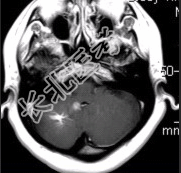

- [材料题] 患者女,41岁。头痛半年,加重10d。头部MRI显示如下图。

- 简答题2、根据该病的影像学表现,该患者可能的诊断是什么?

- 简答题3、为进一步确定诊断,请问下一步的影像学检查是什么?